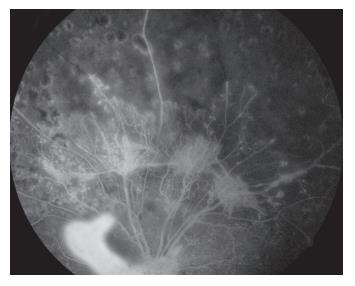

患者女,2 3岁,既往高血压病病史,因“左眼视物模糊1 3天”于2011年4月1 5日就诊于济宁医学院附属医院眼科,眼科查体:右眼视力为0.6,左眼视力为0.08,双眼眼前节情况正常,右眼眼底动脉反光增强,静脉略迂曲(图1),左眼眼底颞上方视网膜大片火焰状出血、棉绒斑、静脉迂曲、黄斑水肿(图2 )。眼底荧光血管造影示:左眼颞上方网膜大片荧光遮蔽,微血管瘤,未见明显无灌注区(图3 ),诊断“左眼视网膜分支静脉阻塞,双眼高血压视网膜病变”,给予随访观察,控制血压。发病36 d时,眼底检查见:左眼视盘新生血管(图4);眼底血管造影检查见:左眼视盘荧光渗漏,颞上视网膜大片无灌注区(图5),给予眼底病变区视网膜激光光凝治疗。发病75 d时,眼底检查见:左眼视盘新生血管增殖膜,颞上方视网膜血管闭塞,散在激光斑(图6,7 ),补充病变区激光治疗。发病103 d时,眼底血管造影检查见:左眼视盘荧光渗漏,颞上方视网膜异常血管网(图8,9 ),补充病变区激光治疗。发病138 d时,左眼视力为0.02,视盘形成新生血管膜,表面血管旺盛(图1 0,11),再次补充病变区激光治疗。1 0年后因“右眼视力下降3天”就诊,查体:右眼视力为0.4,左眼视力为0.4;眼底检查见:左眼视盘新生血管膜机化萎缩,表面无血管(图12),右眼后极部颞下、颞上视网膜棉绒斑,鼻下和鼻侧视网膜浅层出血,鼻上视网膜少许硬性渗出(图13)。

20230106112710_4107.jpg

图3 左眼眼底荧光血管造影见颞上方网膜大片荧光遮蔽,微血管瘤,未见明显无灌注区(发病13 d)

Figure 3 Fluorescein fundus angiography of the left eye showed large fluorescent occlusion, microhemangioma, and no non-perfusion area of the supratemporal retina (oneset of 13 d)